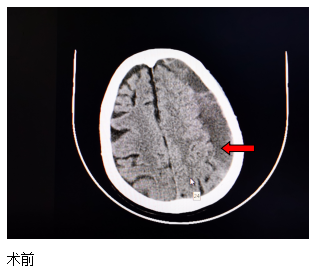

近日,一位84歲高齡患者來(lái)江寧中院就診,表現(xiàn)為:右側(cè)肢體的力量下降、不能獨(dú)立站立、言語(yǔ)不利、吐字不清。經(jīng)頭部CT檢查發(fā)現(xiàn),患者左側(cè)大面積慢性硬膜下血腫,嚴(yán)重壓迫腦組織。

患者收入院后,完善各項(xiàng)檢查,無(wú)明顯手術(shù)禁忌,中醫(yī)院神經(jīng)外科團(tuán)隊(duì)經(jīng)過(guò)精心周全的準(zhǔn)備,為其實(shí)施了腦膜中動(dòng)脈栓塞結(jié)合硬通道血腫穿刺引流的復(fù)合手術(shù)。術(shù)后第二天,患者肢體無(wú)力的癥狀得到了明顯改善,語(yǔ)言表達(dá)也恢復(fù)如初?;颊呒凹覍賹?duì)此治療效果非常滿意。